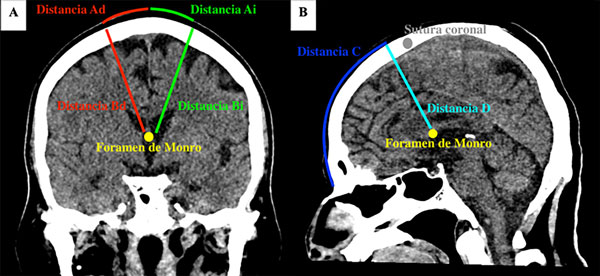

Materiales y métodos: en el análisis de las tomografías se midieron 6 distancias, que se definieron como Ad: de la línea media a la expresión superficial del asta frontal derecha; Bd: del punto Ad al foramen de Monro derecho; Ai: de la línea media a la expresión superficial del asta frontal izquierda; Bi: del punto Ai al foramen de Monro izquierdo; C: entre el nasion y un punto perpendicular que pasa por el foramen de Monro; y D: entre el punto C y el foramen de Monro. Para las mediciones se utilizó el software Horos. Para el análisis estadístico se usó el software Minitab 18 en función de la edad, sexo y lado (derecho o izquierdo).

Las TC cerebrales fueron realizadas en un tomógrafo Toshiba Lightning 16 Achilles con cortes finos de 0.5 mm, en tanto que las mediciones se hicieron utilizando el software Horos versión 3.3.6. Se utilizó el modo de reconstrucción multiplanar (“MPR”) para obtener imágenes volumétricas en incidencia orbitomeatal en el plano sagital y se alinearon los conductos auditivos externos, los peñascos y los globos oculares, tanto en el plano coronal como en el axial. A través de la herramienta ángulo (“angle”) se determinaron los ángulos de 90° empleados en las distintas mediciones. Estas fueron realizadas en el plano coronal con un corte donde se diferenciaban claramente los forámenes de Monro. Para mediciones en el plano sagital, previamente se marcó un espacio entre los dos forámenes de Monro en el plano coronal, logrando una proyección sagital estricta de la ubicación del foramen de Monro (Figura 1).

Figura 1. A) TC en plano coronal que muestra las distancias Ad, Bd, Ai y Bi. En amarillo observamos un punto de referencia entre ambos forámenes de Monro. B) TC en plano sagital que muestra las distancias C y D. El punto amarillo es la referencia marcada previamente en el plano coronal que muestra la ubicación entre ambos forámenes de Monro.

Como puntos de referencia cutáneos se utilizaron el nasion y la línea media (entendida como la línea que une el nasion y el inion, separando el cráneo en dos mitades iguales), se realizaron las siguientes mediciones:

1. Distancia Ad: entre la línea media y un punto cutáneo parasagital derecho en el que, trazando una línea perpendicular a la superficie craneal, dicha línea cruza el asta frontal del ventrículo lateral derecho y llega al foramen de Monro derecho en el plano coronal.

2. Distancia Bd: entre la superficie craneal (proyectada sobre el punto cutáneo parasagital derecho mencionado anteriormente) y el foramen de Monro derecho en el plano coronal.

3. Distancia Ai: entre la línea media y un punto cutáneo parasagital izquierdo en el que, trazando una línea perpendicular a la superficie craneal, dicha línea cruza el asta frontal del ventrículo lateral izquierdo y llega al foramen de Monro izquierdo en el plano coronal.

4. Distancia Bi: entre la superficie craneal (proyectada sobre el punto cutáneo parasagital izquierdo mencionado anteriormente) y el foramen de Monro izquierdo en el plano coronal.

5. Distancia C: entre el nasion y un punto cutáneo sagital (el más cercano a la sutura coronal), en el que, trazando una línea perpendicular a la superficie craneal, dicha línea llega al foramen de Monro en el plano sagital.

6. Distancia D: entre la superficie craneal (proyectada en el punto sagital mencionado anteriormente) y el foramen de Monro en el plano sagital.